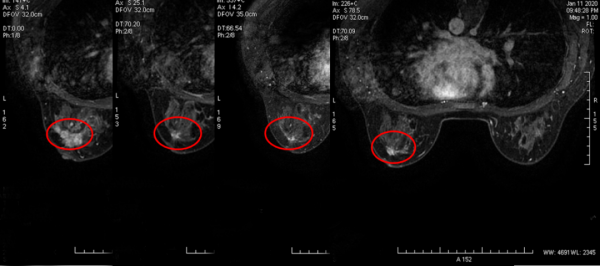

乳腺磁共振:左乳外象限可見不規則性腫塊,呈等T1等T2訊號,範圍約3.1*4.2*4.4cm,增強後呈明顯強化,與鄰近乳頭關係密切,其周圍可見多發強化結節灶,左側乳頭未見明顯內陷,病灶距鄰近胸大肌2.2cm,距離乳腺面板約1.4cm,距離乳頭約0.5cm。左側腋窩可見多發腫大淋巴結,較大者約1.5*1.0cm(圖3)。

2. 乳腺磁共振(6個週期新輔助治療後):與治療前(圖3)相比,原左乳外上象限結節灶大小約0.5*0.9*0.5cm,增強後呈明顯強化,病灶距鄰近胸大肌4.2cm,距離乳腺面板約1.0cm,距離乳頭約1.1cm。左側腋窩未見增大淋巴結(圖5)。